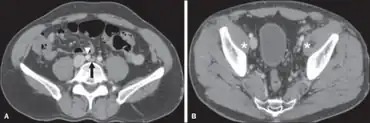

May–Thurner syndrome in the broader disease profile known as nonthrombotic iliac vein lesions (NIVLs) exists in the symptomatic ambulatory patient and these lesions are usually not seen by venography. Morphologically, intravascular ultrasound (IVUS) has emerged as the best current tool in the broader sense.[9] Functional testing such as duplex ultrasound, venous and interstitial pressure measurement and plethysmography may sometimes be beneficial. Compression of the left common iliac vein may be seen on pelvic CT.